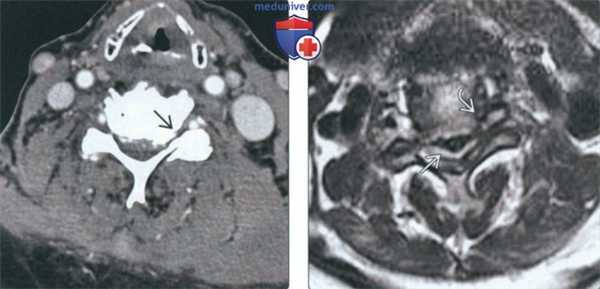

(Слева) КТ, фронтальный срез: признаки выраженной многоуровневой дегенеративной гипертрофической артропатии дугоотростчатых суставов с фораминальным стенозом.

(Справа) КТ, аксиальный срез: признаки выраженного дегенеративного поражения левого дугоотростчатого сустава и фораминального стеноза. В полости дугоотростчатого и унковертебрального сустава отмечается «феномен вакуума».

(Слева) КТ с КУ, аксиальный срез: признаки тяжелого стеноза спинномозгового канала на фоне диффузного пролабирования межпозвонкового диска с вентральными грыжами и кальцификацией диска. Видны признаки выраженного двустороннего фораминального стеноза, гипертрофии унковертебральных суставов и дегенерации дугоотростчатых суставов.

(Справа) Т2-ВИ, аксиальная проекция: выраженное истончение спинного мозга, проявляющееся относительным усилением сигнала и связанное с его импинджментом между межпозвонковым диском и остеофитами вентрально и утолщенной отличающейся низкой интенсивностью сигнала желтой связкой дорзально. Также видны признаки выраженного двустороннего фораминального стеноза.

(Слева) На корональной КТ без КУ определяется тяжелая многоуровневая гипертрофическая дегенеративная артропатия дугоотростчатых суставов со стенозом межпозвонковых отверстий.

(Справа) На аксиальной КТ без КУ определяется тяжелая левосторонняя дегенеративная артропатия дугоотростчатого сустава со стенозом межпозвонкового отверстия. Определяется вакуум - феномен дугоотростчатого сустава и унковертебрального сустава.

(Слева) На аксиальной КТ с КУ определяется тяжелый стеноз позвоночного канала, обусловленный диффузными грыжами диска на широком основании с сопутствующим обызвествлением диска. Определяется также выраженный двухсторонний стеноз межпозвонковых отверстий в сочетании с гипертрофией унковертебральных суставов и дегенеративными изменениями суставных отростков.

(Справа) На аксиальной MPT (Т2 ВИ) определяется выраженное истончение спинною мозга с относительно гиперинтенсивным сигналом, ограниченною спереди диском и остеофитами, сзади - утолщенными желтыми связками с гипоинтенсивным сигналом. Определяется выраженный стеноз обоих межпозвонковых отверстий.